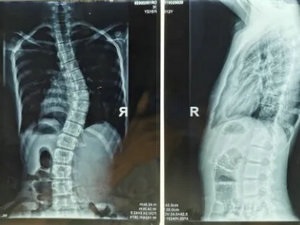

02 影像学检查

1.脊柱侧弯筛查需站立位全脊柱X光片正侧位。

2.骨盆前倾:矢状面 Cobb 角>50°。